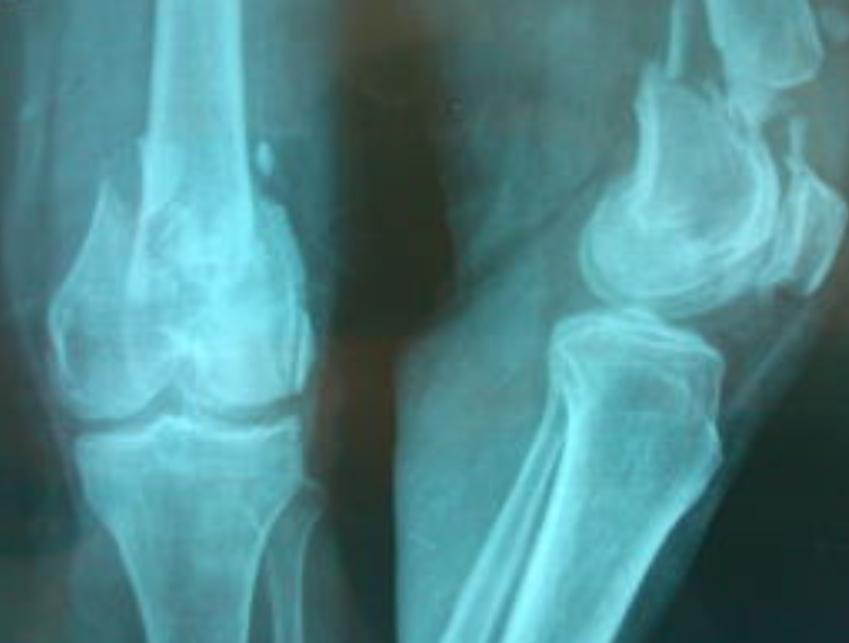

股骨远端骨折情况复杂的,骨折线常常累及关节面,要做到良好的复位,合理的固定是有一定难度的。合 并复杂软组织损伤的病例更是对医生的一种考验。

RIN的应用有一定局限性,适用于股骨远端A型、C1型、C2型和部分C3型骨折, 对复杂的髁间粉碎性骨折难以进行有效固定, 也有学者认为C2、C3型骨折是逆行髓内钉相对禁忌症。